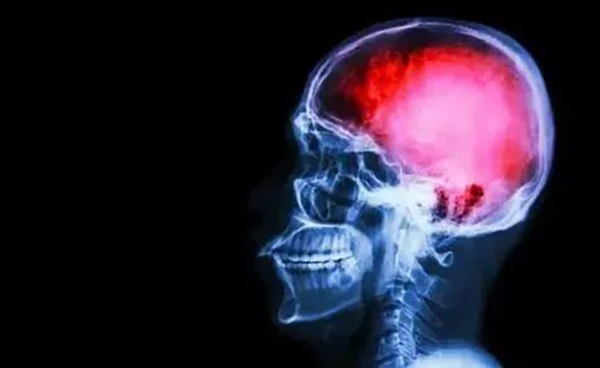

关于脑卒中,这是一篇最全科普,人人都应当学习!

脑卒中到底是什么?

脑卒中的定义为急性脑血管病引起的局部脑功能障碍,其临床症候持续超过24小时。卒中包括缺血性卒中和出血性卒中,缺血性卒中又称脑梗死,包括脑血栓形成和脑栓塞,占卒中的85%。

如果缺血性脑血管病的症候持续时间<24小时,称为短暂性脑缺血发作。出血性卒中是因脑血管出血所致,出血性卒中占卒中的15%。

大脑控制着整个身体,所以卒中的症状遍布全身。具体出现什么症状,取决于脑组织受损的部位。